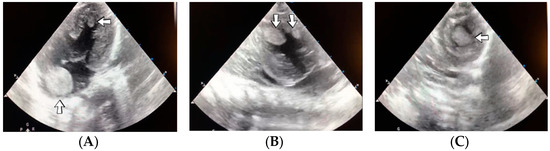

4.36. Case No. 36—Postnatal Intracardiac Thrombosis

A 7-week-old male infant (36 weeks, 2.50 kg), the first twin from a twin pregnancy, presented with a complex congenital cardiac malformation for an elective surgical procedure (Blalock–Taussig shunt). Heparin infusion for the shunt was started immediately after the intervention and anticoagulation was continued with enoxaparin due to good clinical condition. Then, 18 days after the procedure, a routine cardiovascular ultrasound revealed a thrombus in the left ventricle (Figure 16). The laboratory studies showed leukocytosis, highly elevated c-reactive protein, and modified coagulation tests (due to anticoagulant treatment). Continuous heparin infusion was reinitiated, but multiple intracardiac thrombi were detected during the following days. Treatment with alteplase was also started, but the patient’s condition continued deteriorating, leading to a negative outcome due to cardiac failure.

Figure 16.

Intracardiac thrombosis identified on cardiac ultrasound: left atrium and ventricle (A), left ventricle (B), apex (C).

Genetic testing confirmed inherited thrombophilia, with positive PAI-1 4G/5G promoter, MTHFR A1298C homozygous gene mutations, and Antithrombin and Protein C deficiencies. There was no known family history of thrombophilia. The mother had a previous therapeutic abortion due to a prenatal diagnosis of a complex congenital cardiac malformation.